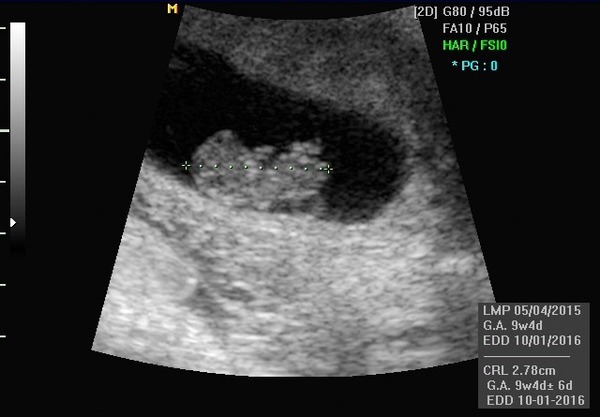

As promised scan pick below.

Lovely scan photo niff

Niff I can't see scan photo on app but glad it went well!

nif great pic, almost looks like it's sucking its thumb!